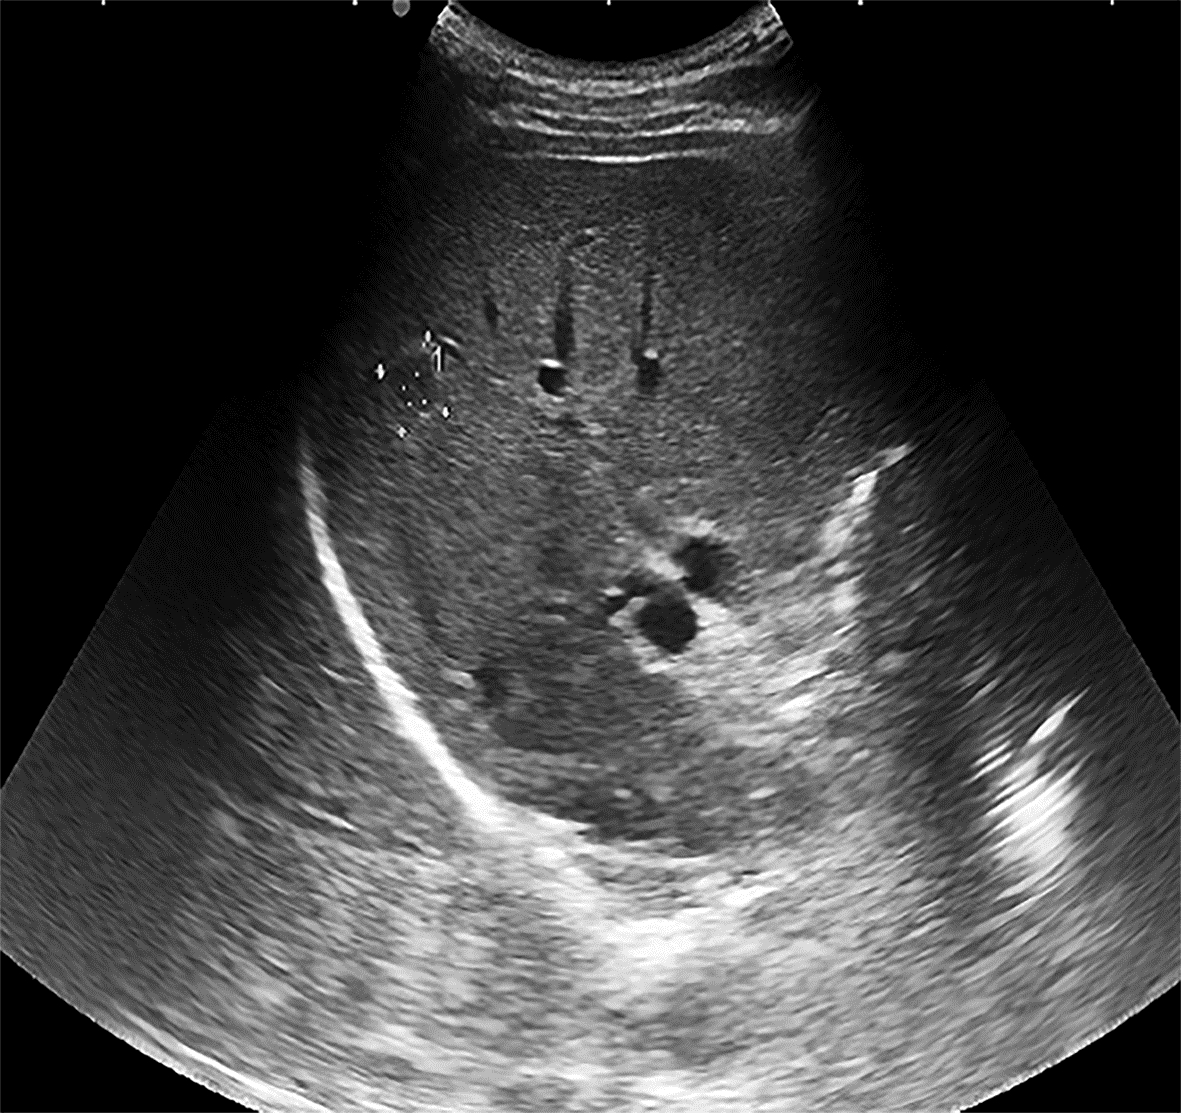

Value of 18F-FDG PET/CT, contrast-enhanced ultrasound, and their combined use in differential diagnosis of benign and malignant pancreatic lesions: A comparative study

Lichun ZHENG, Xiaoming ZHANG, Tianying YU, Jie LI, Xiaoqian DENG, Xiangliu OUYANG

2022, 38(12): 2774-2779. DOI: 10.3969/j.issn.1001-5256.2022.12.017

Abstract(2246) HTML (1599) PDF (3391KB)(53)

Abstract:

Objective  To assess the value of 18F-FDG PET/CT, contrast-enhanced ultrasound, and their combination in the differential diagnosis of benign and malignant pancreatic lesions.  Methods  A retrospective analysis was performed on patients with pancreatic lesions who underwent18F-FDG PET/CT and contrast-enhanced ultrasound who were admitted to Tangshan Gongren Hospital from January 2015 to December 2020. The imaging results were confirmed by pathology examination to evaluate diagnostic sensitivity, specificity, accuracy, positive and negative predictive value. The t-test was used for comparison of continuous data between two groups, and the chi-square test was used for comparison of categorical data between groups.  Results  There were 83 malignant lesions and 25 benign lesions in 108 patients. The sensitivity, specificity, accuracy, positive and negative predictive value were 86.75%, 80.00%, 85.19%, 93.51% and 64.52% for 18F-FDG PET/CT; and 69.88%, 76.00%, 71.30%, 90.63% and 43.18% for contrast-enhanced ultrasound, respectively. The two methods differed significantly in sensitivity and accuracy (all P < 0.05), but not in specificity, negative and positive predictive value (all P > 0.05). When combined with the contrast-enhanced ultrasound, 18F-FDG PET/CT had an increased sensitivity, specificity, accuracy, positive and negative predictive value of 90.36%, 84.00%, 88.89%, 94.94% and 72.41%, respectively, though this was not statistically significant due to the increased signal of blood supply in the lesions.  Conclusion  18F-FDG PET/CT has a better performance than contrast-enhanced ultrasound in the differential diagnosis of benign and malignant pancreatic lesions, and their combination can improve the diagnostic value.